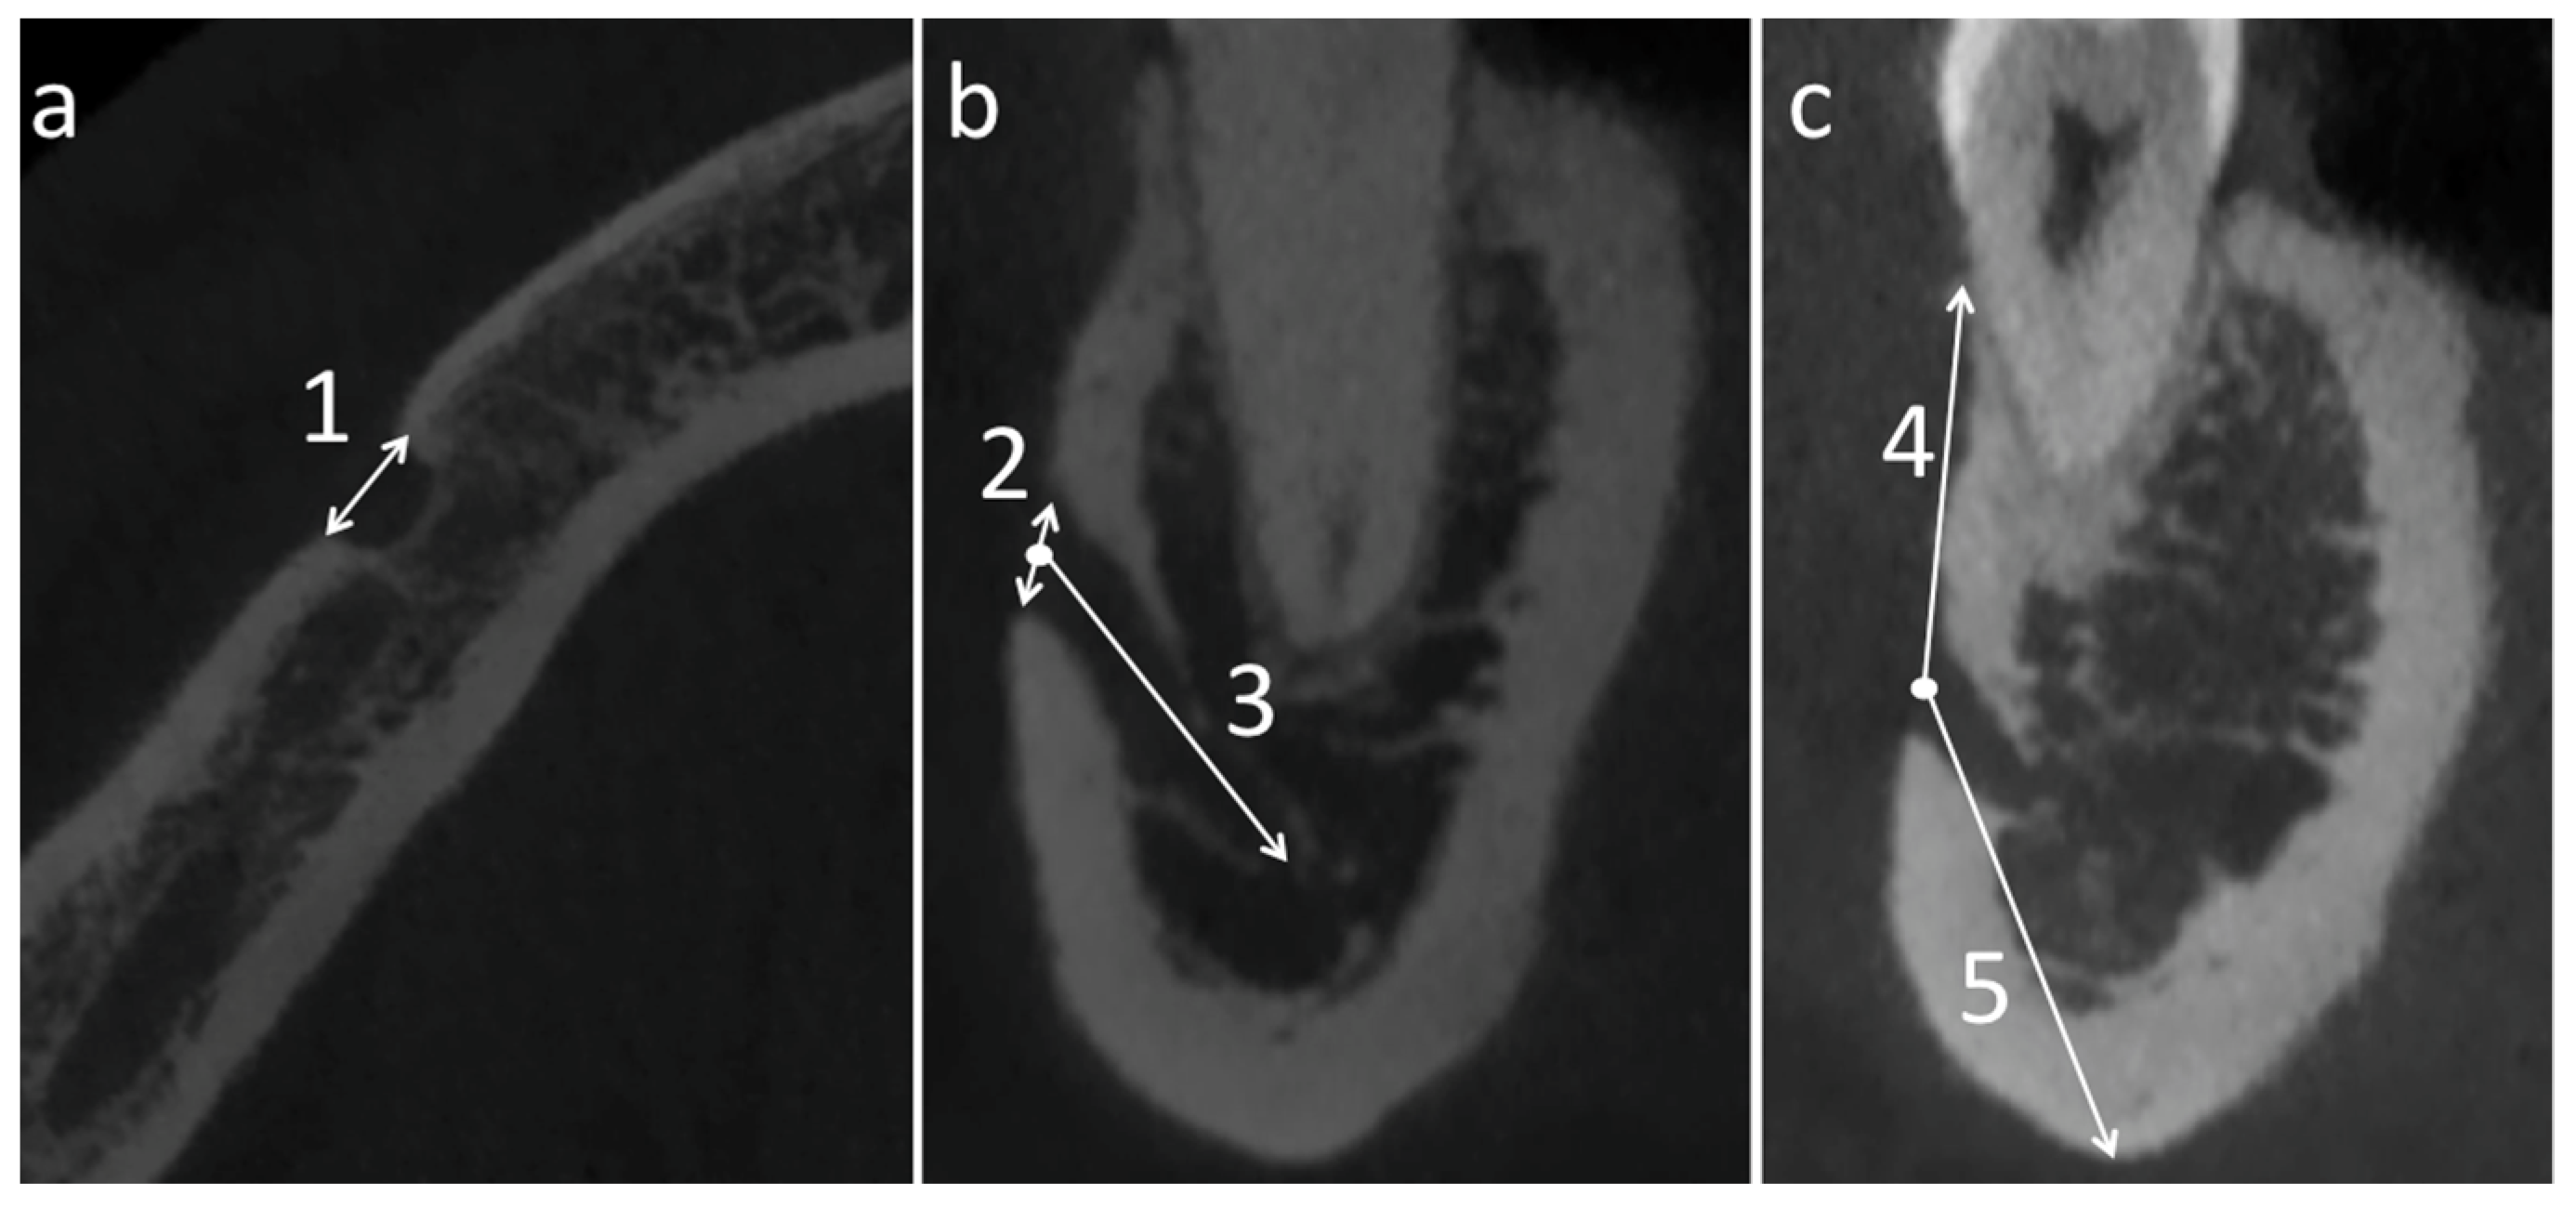

- Width of the MF in the transverse axial section;

- Height of the MF in the coronal section;

- Depth of the MF in the coronal section (distance between the center and the deepest point of the MF);

- Distance of the center of the MF from the inferior mandibular edge in the coronal section;

- Distance of the center of the MF from the superior mandibular edge in the coronal section.